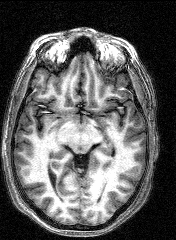

The last session involved several MRI and fMRI scans while completing tasks in the noisy environment of the scanner. Thanks to a friend who worked at the Institute, I was able to secure a copy of the raw data and an application to turn it into images, some of which are displayed here.

The images to the right are virtual 'slices', taken horizontally, starting from the top and working down. Cerebrospinal fluid is dark, the white matter appears light.